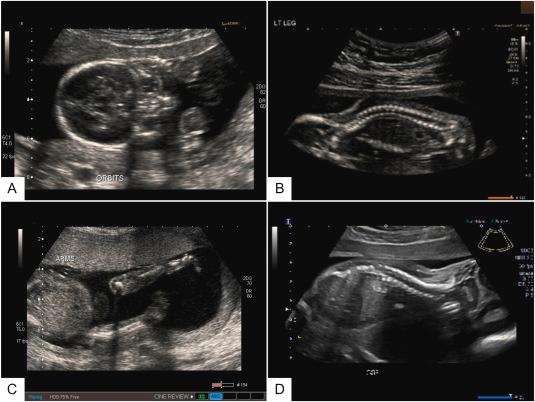

● Standard planes for HC/AC/FL and common pitfalls

● Anatomy screening essentials and documentation